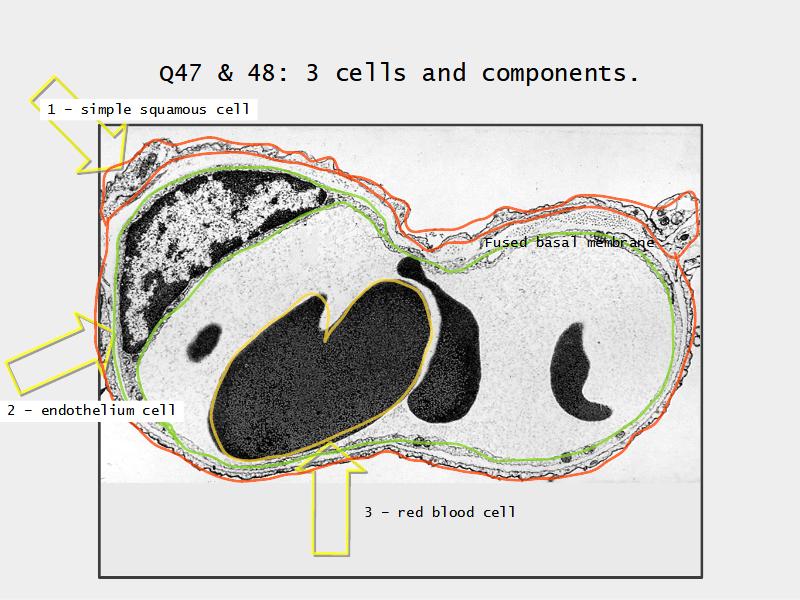

What cells are present?

Components of the Blood-Air Barrier?